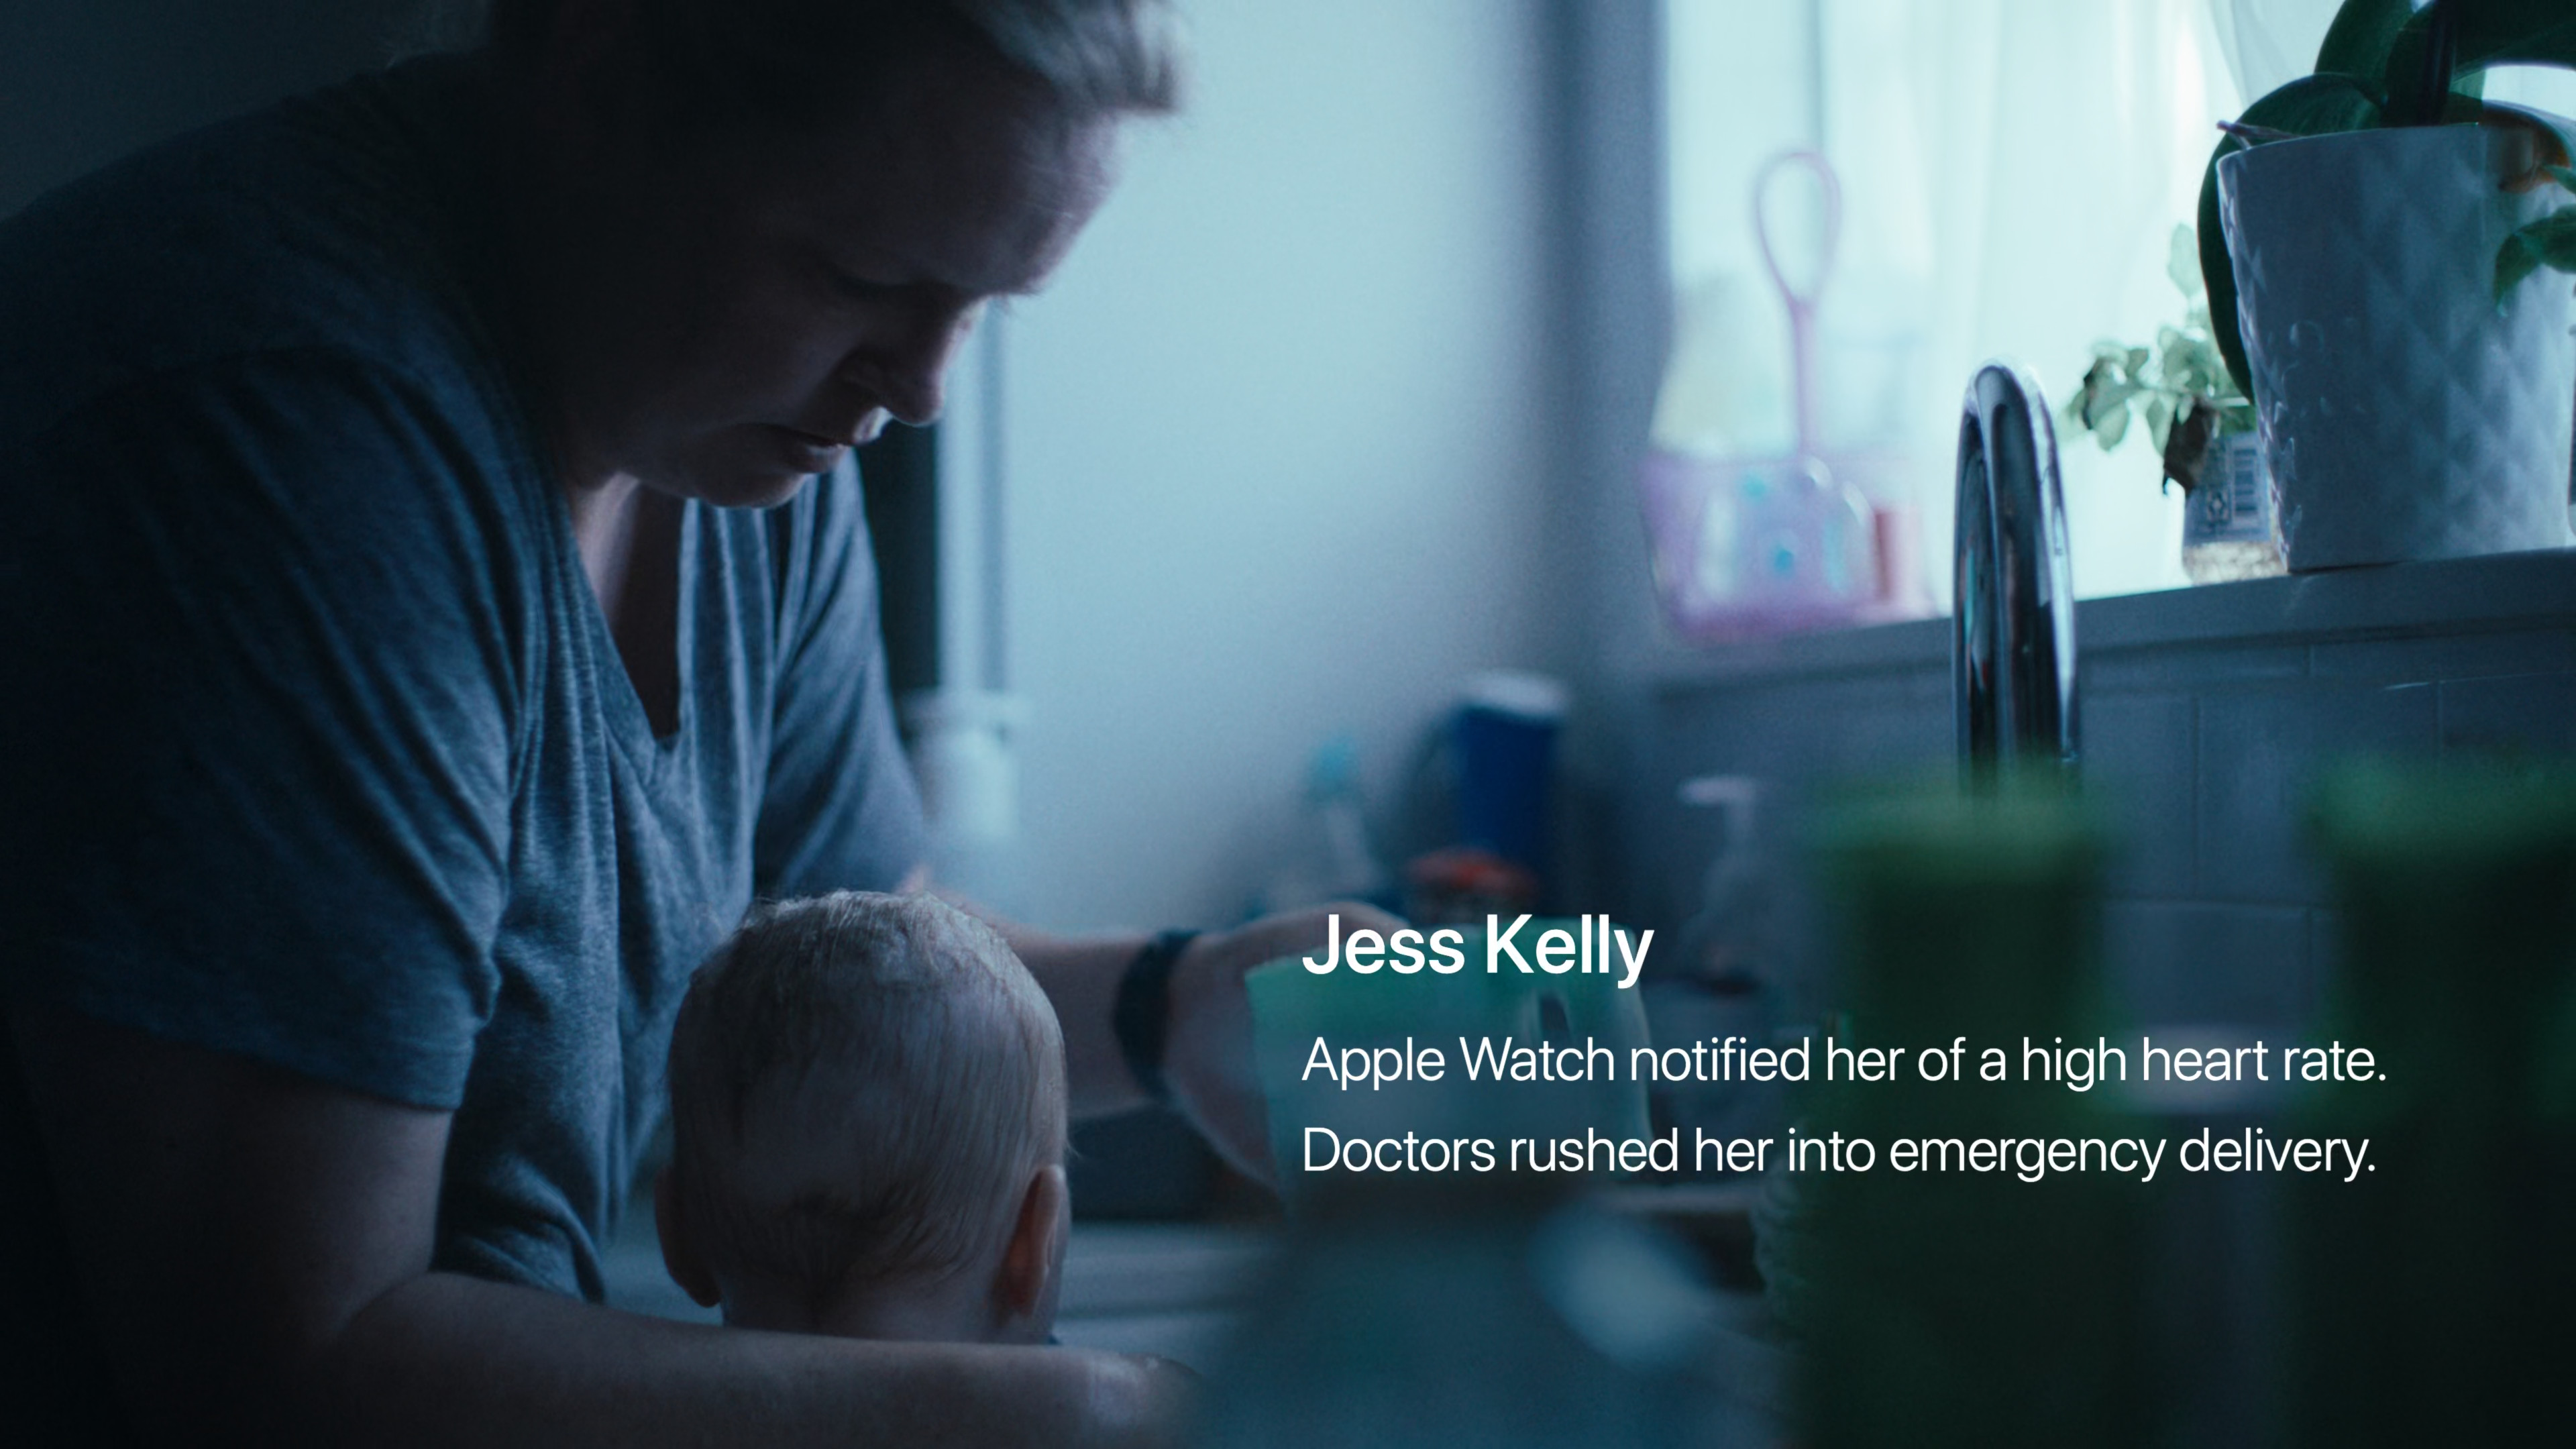

Již několik desítek minut před začátkem se na webu Applu objevilo logo letošní Keynote za doprovodu skladby Natural od Jackie Mendozy a Magic in U od Cub Sport. Jakmile odbila sedmá, animace se změnila v tradiční úvodní video se záběry na různé lidi, jak v průběhu dne od probuzení až do noci používají nejrůznější Apple zařízení. Po přehrání emotivního videa, zmiňujícího mimo jiné přínos Apple Watch a dalších jablečných produktů a jejich funkcí pro lidské zdraví, jsme se mohli pokochat klasickým přeletem nad Apple Parkem. V němž nás již přivítal Tim Cook a zahájil nejdůležitější Apple Keynote letošního roku, na které se představí iPhone 15, iPhone 15 Pro (Max), Apple Watch Series 9 a spousta dalších novinek.